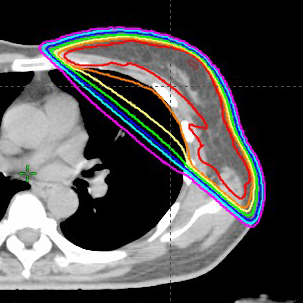

左乳がん術後照射乳がん術後照射,66Gy/33回 大きな機械をまじまじと見ていたら、それに気付いた技師の方が機械の説明をしてくれました。機械的な対応にならず、私の意図をくみ取っていただいたので嬉しかった・・・(つづきを読む) |

右乳がん術後照射乳がん術後照射,66Gy/33回 放射線治療は33回もあり、猛暑の中通院はきつかったですが、同じ患者さん同士で励まし合ったり、愚痴を言い合うことで私自身大きく助けられたと感じ・・・(つづきを読む) |

右乳がん術後照射乳がん術後照射,50Gy/25回 患者さんの感想:暑い毎日で、25回の通院で大変だな~と思いましたが、決められた予約の時間ではなく、自分の都合に合わせて通院できたことが良かったです。毎日大体同じ時間に・・・(つづきを読む) |

右乳がん術後照射乳がん術後照射,50Gy/25回 患者さんの感想:病気の告知を受けて一人深刻に思い悩む日もありましたが、放射線科での治療が始まってからは毎日同じ時間帯に顔を合わせる人達と挨拶を交わし、会話をすることで気持ちがだんだん・・・(つづきを読む) |

左乳がん術後照射乳がん術後照射,50Gy/25回 患者さんの感想:納得して放射線治療を受診することができました。事前の説明は大変参考になり不安が解消されました。最初CTを撮った時が一番不安でしたが、技師の方達の緊張をほぐしてくれながらの対応でほっとした・・・(つづきを読む) |

右乳がん術後照射乳がん術後照射,66Gy/33回 患者さんの感想:毎日患部を見せなくてはならないことでの羞恥心やストレスがありました。男性の技師さんのさりげない配慮や女性の技師さんが1人居て下さるだけで、後半はストレスもなく治療を受けることができ・・・(つづきを読む) |

右乳がん術後照射乳がん術後照射,50Gy/25回 患者さんの感想:手術、又術後も何事もなかった様に生活をしています。気持ちを前向きにもち、往復2時間の通院で車を運転し、好きな音楽を聴き、コーヒーを飲みながら無事に25回の放射線治療を完了・・・(つづきを読む) |

右乳がん術後照射乳がん術後照射,50Gy/25回 患者さんの感想:放射線治療を受けるにあたり事前の説明をきちんとわかりやすく丁寧にして頂き、看護師さん・医師・技師の先生方、受付の方も一方的にならず、私のペースに合わせ寄り添って話を聴いて頂け・・・(つづきを読む) |